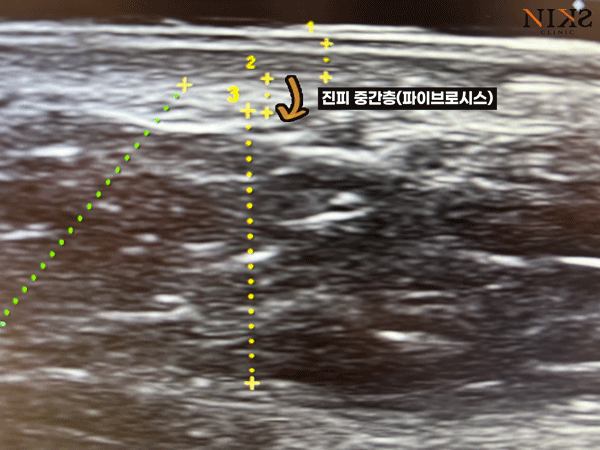

초음파 이미지로 설명드리자면

가장 윗층이(1번 부분) 피부의 표피 ~ 진피 상부,

2에서 3번 부분이 진피 중간층입니다.

그 아래쪽의 어두운 부분은 지방층인데요, 이렇게 딱 보기에도

피부와 지방 사이를 “지지하는”층이라는게 눈에 들어오죠?